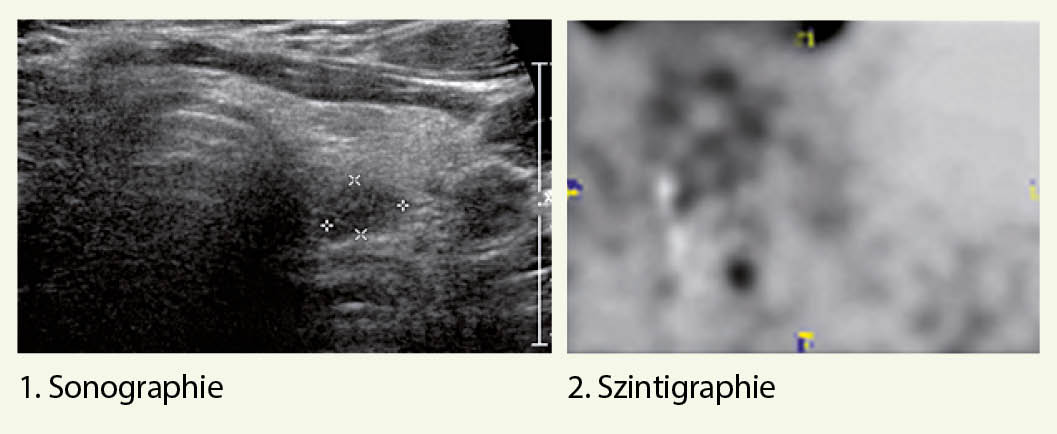

Eine erfolgreiche Lokalisationsdiagnostik ermöglicht einen fokussierten und dadurch auch minimal-invasiven operativen Zugangsweg (16) und schliesst als Optionen 1. die zervikale Sonographie und 2. die Sestamibi-Szintigraphie bzw. Sestamibi-SPECT/ CT-Untersuchung mit ein.

Bei fehlender Lokalisation in der Sonographie und Szintigraphie oder auch bei diskordanten Befunden, steht neuerdings das Cholin-PET zu Verfügung, das eine erhöhte Sensitivität hat und entsprechend eine tiefere falsch-negative Rate (17).